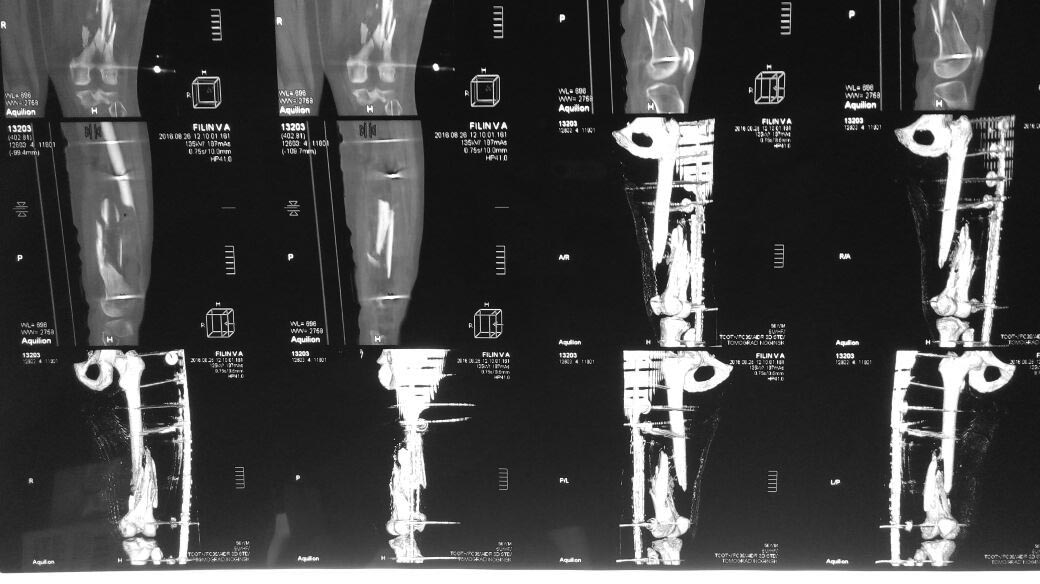

Уважаемые коллеги подскажите как бы вы поступили в данном случае дальше?Травма 2 августа. О/перелом бедра. Рана была на передней пов. бедра 5 см., протекала с серозным отделяемым (дренажи, вторичная х.о., а/б...).

Швы сняты 26.08.Кожа без воспаления. Температура в пределах 36 утром 37.1 вечером.В области мыщелков бедра стержень дает серозное отделяемое. Мужчина трудоспособного возраста. Примерно под 100кг..

Для низкого многооскольчатого перелома бедра интрамедуллярный остеосинтез возможное, но наверное не самое лучшее решение. Тут ИМХО все же лучше длинная пластина из небольших доступов.

Закрытый интрамедллярный остеосинтез. Скорее бы антеградно, fixator-assisted. Стержень покрыть цементом с ваномицином.